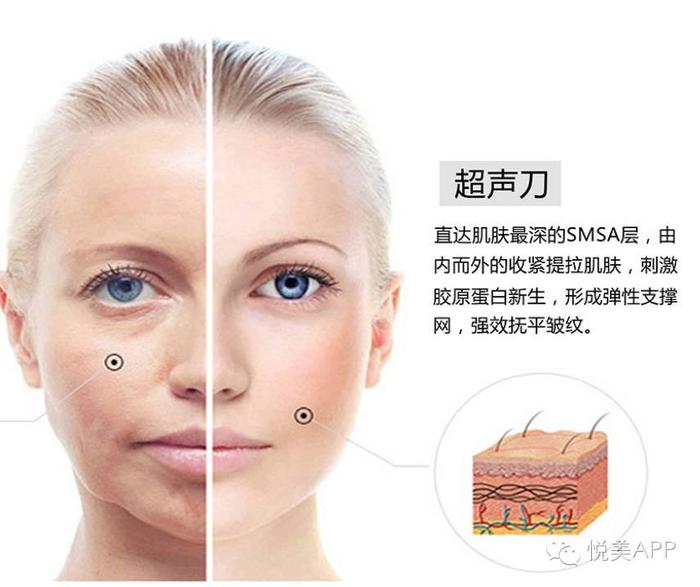

2、超声刀、埋线提升

刺激胶原蛋白新生,拉紧皮肤